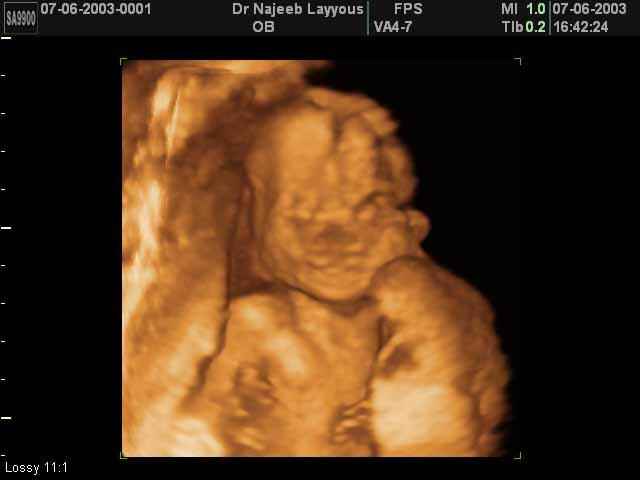

3D second trimestre échographie Photos de numérisation - deuxième partie de la grossesse | Dr N Layyous

3D second trimestre échographie Photos de numérisation - deuxième partie de la grossesse